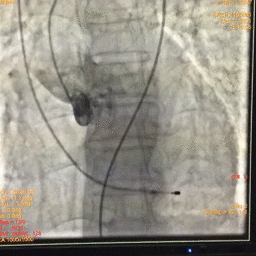

图片

根部造影

球囊预扩

瓣膜释放

瓣膜释放完毕

手术结果

术后造影及超声探查未见瓣周漏,跨瓣压差术前56mmHg,术后几乎无压差,术中及术后未出现相关并发症,手术圆满完成。